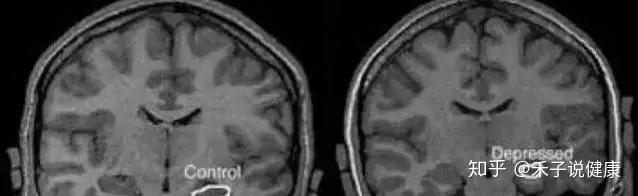

1.抑郁症患者的大脑和正常人大脑对比。

随着脑成像技术越来越发达,现在医生和脑科学家可以用强大的核磁共振机器观察到一个人即时的大脑活动和大脑结构。随着最近十年大脑成像数据的积累,精神病学家终于解读出了精神病相关的大脑活动。这个先进的方法可以让我们看到,当一个人集中注意力的时候,大脑的前额叶活跃程度就会变高,在核磁共振图像上的显示,就是前额叶会比其他区域更亮;或者当一个人感到恐惧焦虑时,他大脑中央深处的杏仁核就会活跃,从核磁共振图像上来看,就是杏仁核区域特别闪亮。

抑郁患者(左)的杏仁核区域(中间)明显很亮

2.抑郁症病人大脑的海马体体积比没有抑郁症的人明显更小。

海马体是我们大脑当中负责记忆和认知功能最核心的区域,也涉及到一些情绪功能。很多神经科学家认为,海马体和周边的脑区是人类大脑在成年之后唯一还有神经再生的区域。这个区域的萎缩通常对应着记忆力衰退、认知能力的下降和抑郁的情绪状态。

正常大脑(左)与抑郁症患者大脑(右)海马体大小对比如果得不到及时的治疗,抑郁症持续的时间越久,大脑海马体的体积就可能越小。而如果抑郁症得到及时治疗,海马体的体积也会有所恢复。